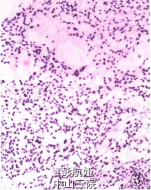

入院后行病理检查见右颈内静脉见癌栓,心脏扇扫显示左房占位,CT示肺内多数小点状阴影,考虑甲状腺癌转移,行左心房肿物切除术。术中见左房内肿物与房壁无关,肿物由肺静脉内长出,另见肺静脉内多发肿物。术中将左房内肿物送快速病理检查。眼观:肿物大小9 cm×7 om×5 cm,切面灰白色,黏液样,部分质韧,部分质软。镜检:黏液样物质背景下见肿瘤细胞呈梭形及圆形,呈团巢状、网格状排列,未见核分裂象。术中快速冷冻病理诊断:间叶源性肿瘤,部分区域细胞增生活跃,考虑肌源性可能性大。术后肿物行病理检查,镜下见肿瘤细胞呈梭形、圆形,细胞核较大,呈团巢状、网状排列,核分裂象少见,间质少,有大量粉染无结构物质,局部见大量坏死。免疫表型:vimentin、CK、TTF一1均(+++),Ki-67增殖指数<5%,Syn(灶状+),S-100、desmin、Myod.1、CR、HEMB一1、CKl9、SMA、p53、p63、Galectin-3、CK5/6、CK8/18、TG均(一),CT(+)(图4),刚果红染色:淀粉样物阳性

病理诊断:恶性肿瘤,结合病史及免疫表型考虑为甲状腺髓样癌转移癌栓。